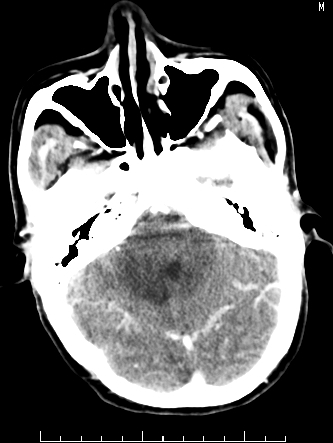

m/50,头昏头痛1月,近3天感觉左半肢体活动不利,自述半年前呈患肺tb,腰穿脑脊液未见特殊改变。现做头颅ct请大家会诊。

ct值?是囊变?梗塞软化灶形成

考虑颅内感染性病变:结核可能性大。

结核性脑膜炎,结核瘤,梗塞灶三症并存,提示颅内结核感染可能性大。